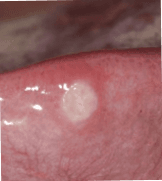

Bilder på afteblåsor

Afteblåsor, även kallade aftös stomatit när flera dyker upp samtidigt, är små smärtsamma sår eller blåsor som uppstår på insidan av munnen, på tungan, insidan av kinderna eller på tandköttet. De är vanliga och helt ofarliga, men de kan vara väldigt besvärande. Afteblåsor är inte smittsamma och brukar försvinna av sig själva inom en till två veckor.

Små, runda eller ovala sår eller blåsor med en vit eller gulaktig yta, samt röd kant.